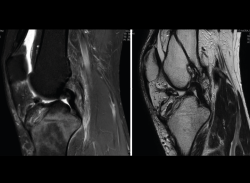

4.3. Osteocondritis

En la osteocondritis se aprecia una lesión subcondral caracterizada por resorción ósea, colapso y la formación de un secuestro.

El estudio por RM es una herramienta valiosa para diagnosticar e identificar las lesiones del cartílago. Conocer el aspecto del cartílago y saber cuánto y cuándo se lesiona, basándose en las clasificaciones actuales, permiten al radiólogo proporcionar la máxima información al clínico(20).

Figura 53. Corte de secuencia sagital (A) y axial (B) T2 Fat-Sat de RM de rodilla: lesiones osteocondrales en el fémur y la rótula.

Numerosos estudios demuestran la utilidad de la RM para definir la estabilidad o inestabilidad de la lesión en la osteocondritis, destacando su carácter no invasivo y la capacidad de valorar la progresión y la respuesta al tratamiento(21)(Figuras 53 y 54).

Figura 54. Corte de secuencia T1 y T2 Fat-Sat coronal de resonancia magnética: gran osteocondritis en el cóndilo femoral interno con edema en la medular adyacente.